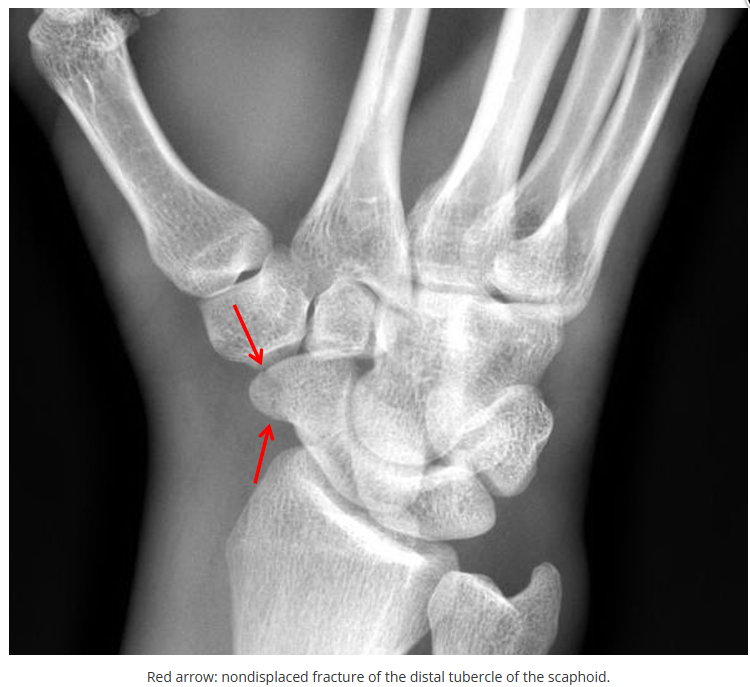

今天是腕部与手的X线片。所有X线片都

带有标注和说明

,可以选择长按图片,

自动翻译相关说明

。